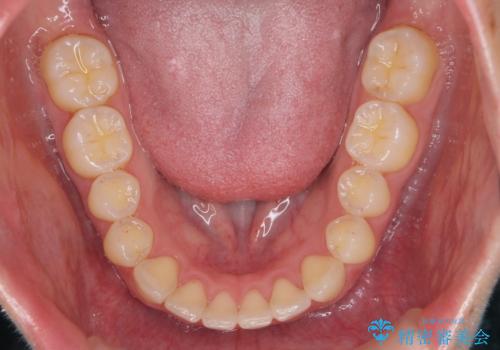

下の前歯が1本短い インビザラインと部分矯正の組み合わせ

- 前歯のガタつきと、下の前歯が一本短いことを主訴に来院。

インビザラインのマウスピースではめる装置で歯を引っ張り出すことは難しいと説明し、下の前歯だけワイヤー部分矯正を行ってからインビザライン矯正で仕上げをしました。